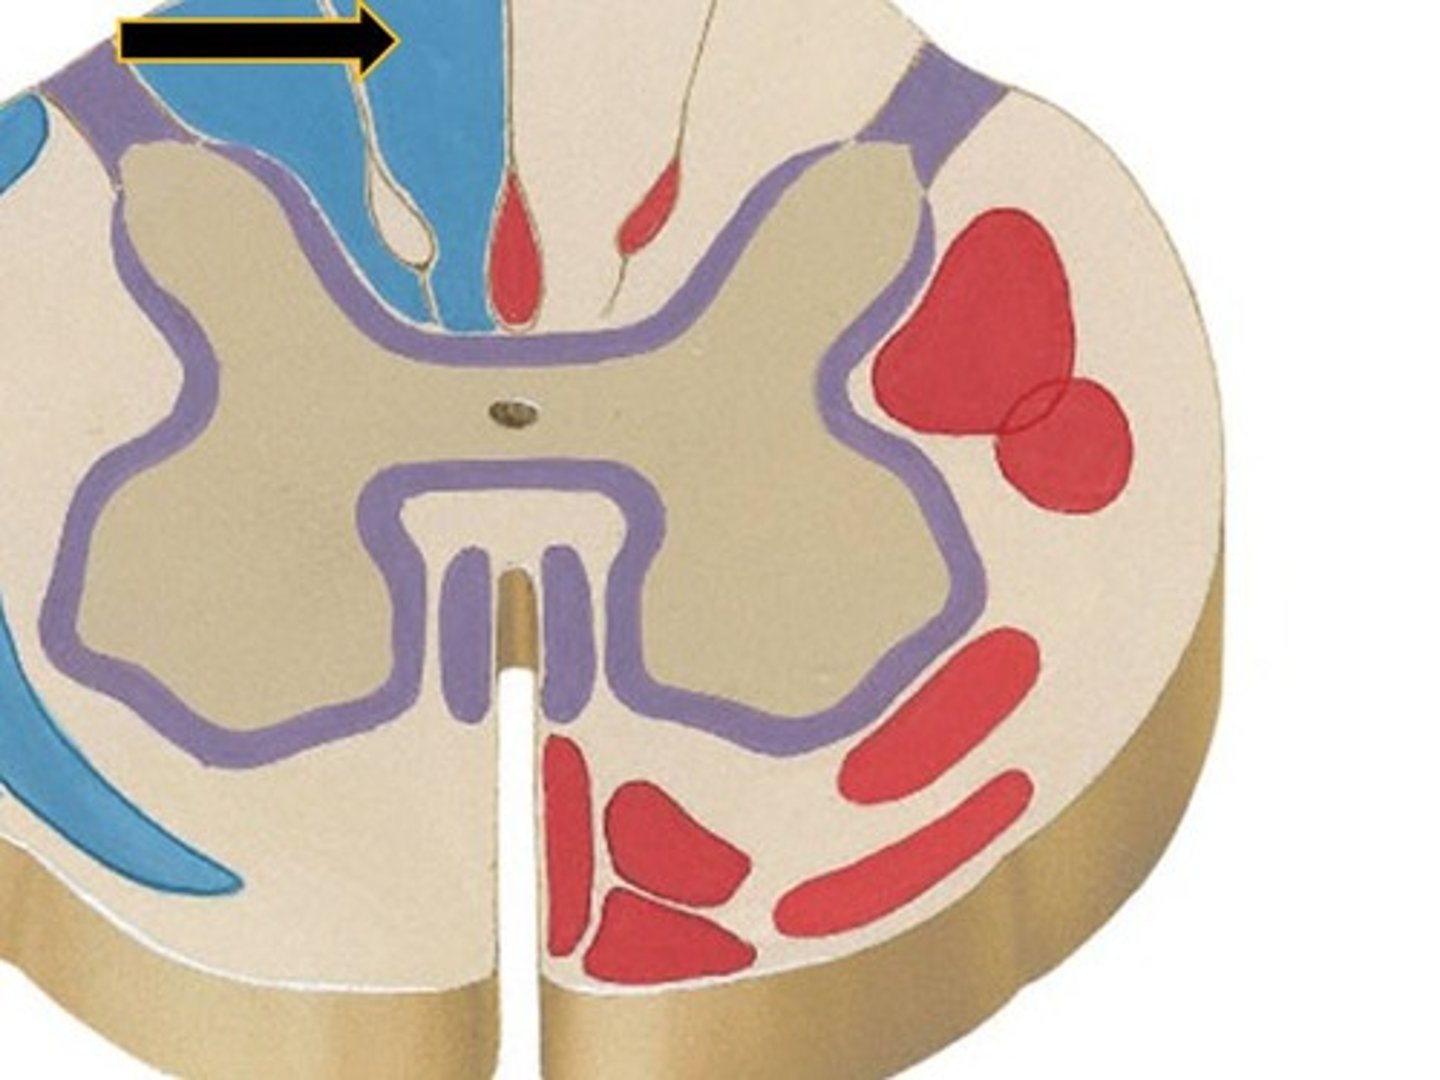

grey matter

(in orange)

dorsal horn

lateral horn

ventral horn

dorsal median sulcus

ventral median fissure

grey commissure

central canal

white matter

dorsal column

lateral column

ventral column

fasciculus gracilis

fasciculus cuneatus

dorsal spinocerebellar tract

dark green, #5

lateral spinothalamic tract

lateral corticospinal tract